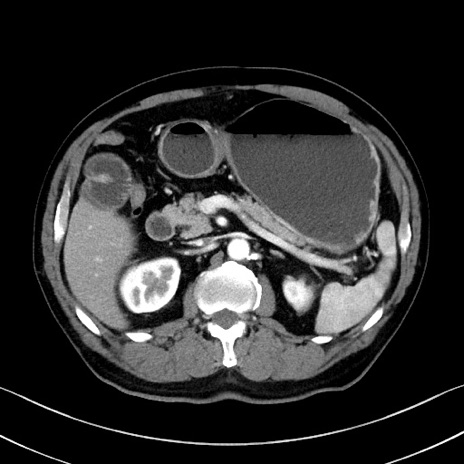

症例35(横断像)

【症例】70歳代 男性

【主訴】腹部膨満、嘔吐

【現病歴】昨日より腹部膨満感出現。本日増悪し、仙痛出現。嘔吐あり、受診。

【既往歴】糖尿病、胆摘後

【身体所見】BP 149/80mmHg、HR 74/min、BT 35.9℃、腹部:膨満、軟、圧痛なし。腸雑音減弱あり。上腹部正中切開瘢痕あり。

【データ】WBC 13500、CRP 1.72